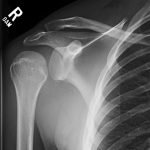

Radiographs demonstrated posterior displacement of the humeral head on the “Y” view (see white arrow) and widening of the glenohumeral joint space on anterior-posterior view (see red arrow). The findings were consistent with posterior dislocation and a Hill-Sachs type deformity. Sedation was performed and reduction was attempted using external rotation, traction counter-traction. An immediate “pop” was felt during the procedure. Post-procedure radiographs revealed a persistent posterior subluxation with interlocking at posterior glenoid. CT revealed posterior dislocation with acute depressed impaction deformity medial to the biceps groove with the humeral head perched on the posterior glenoid, interlocked at reverse Hill-Sachs deformity (see blue arrow).